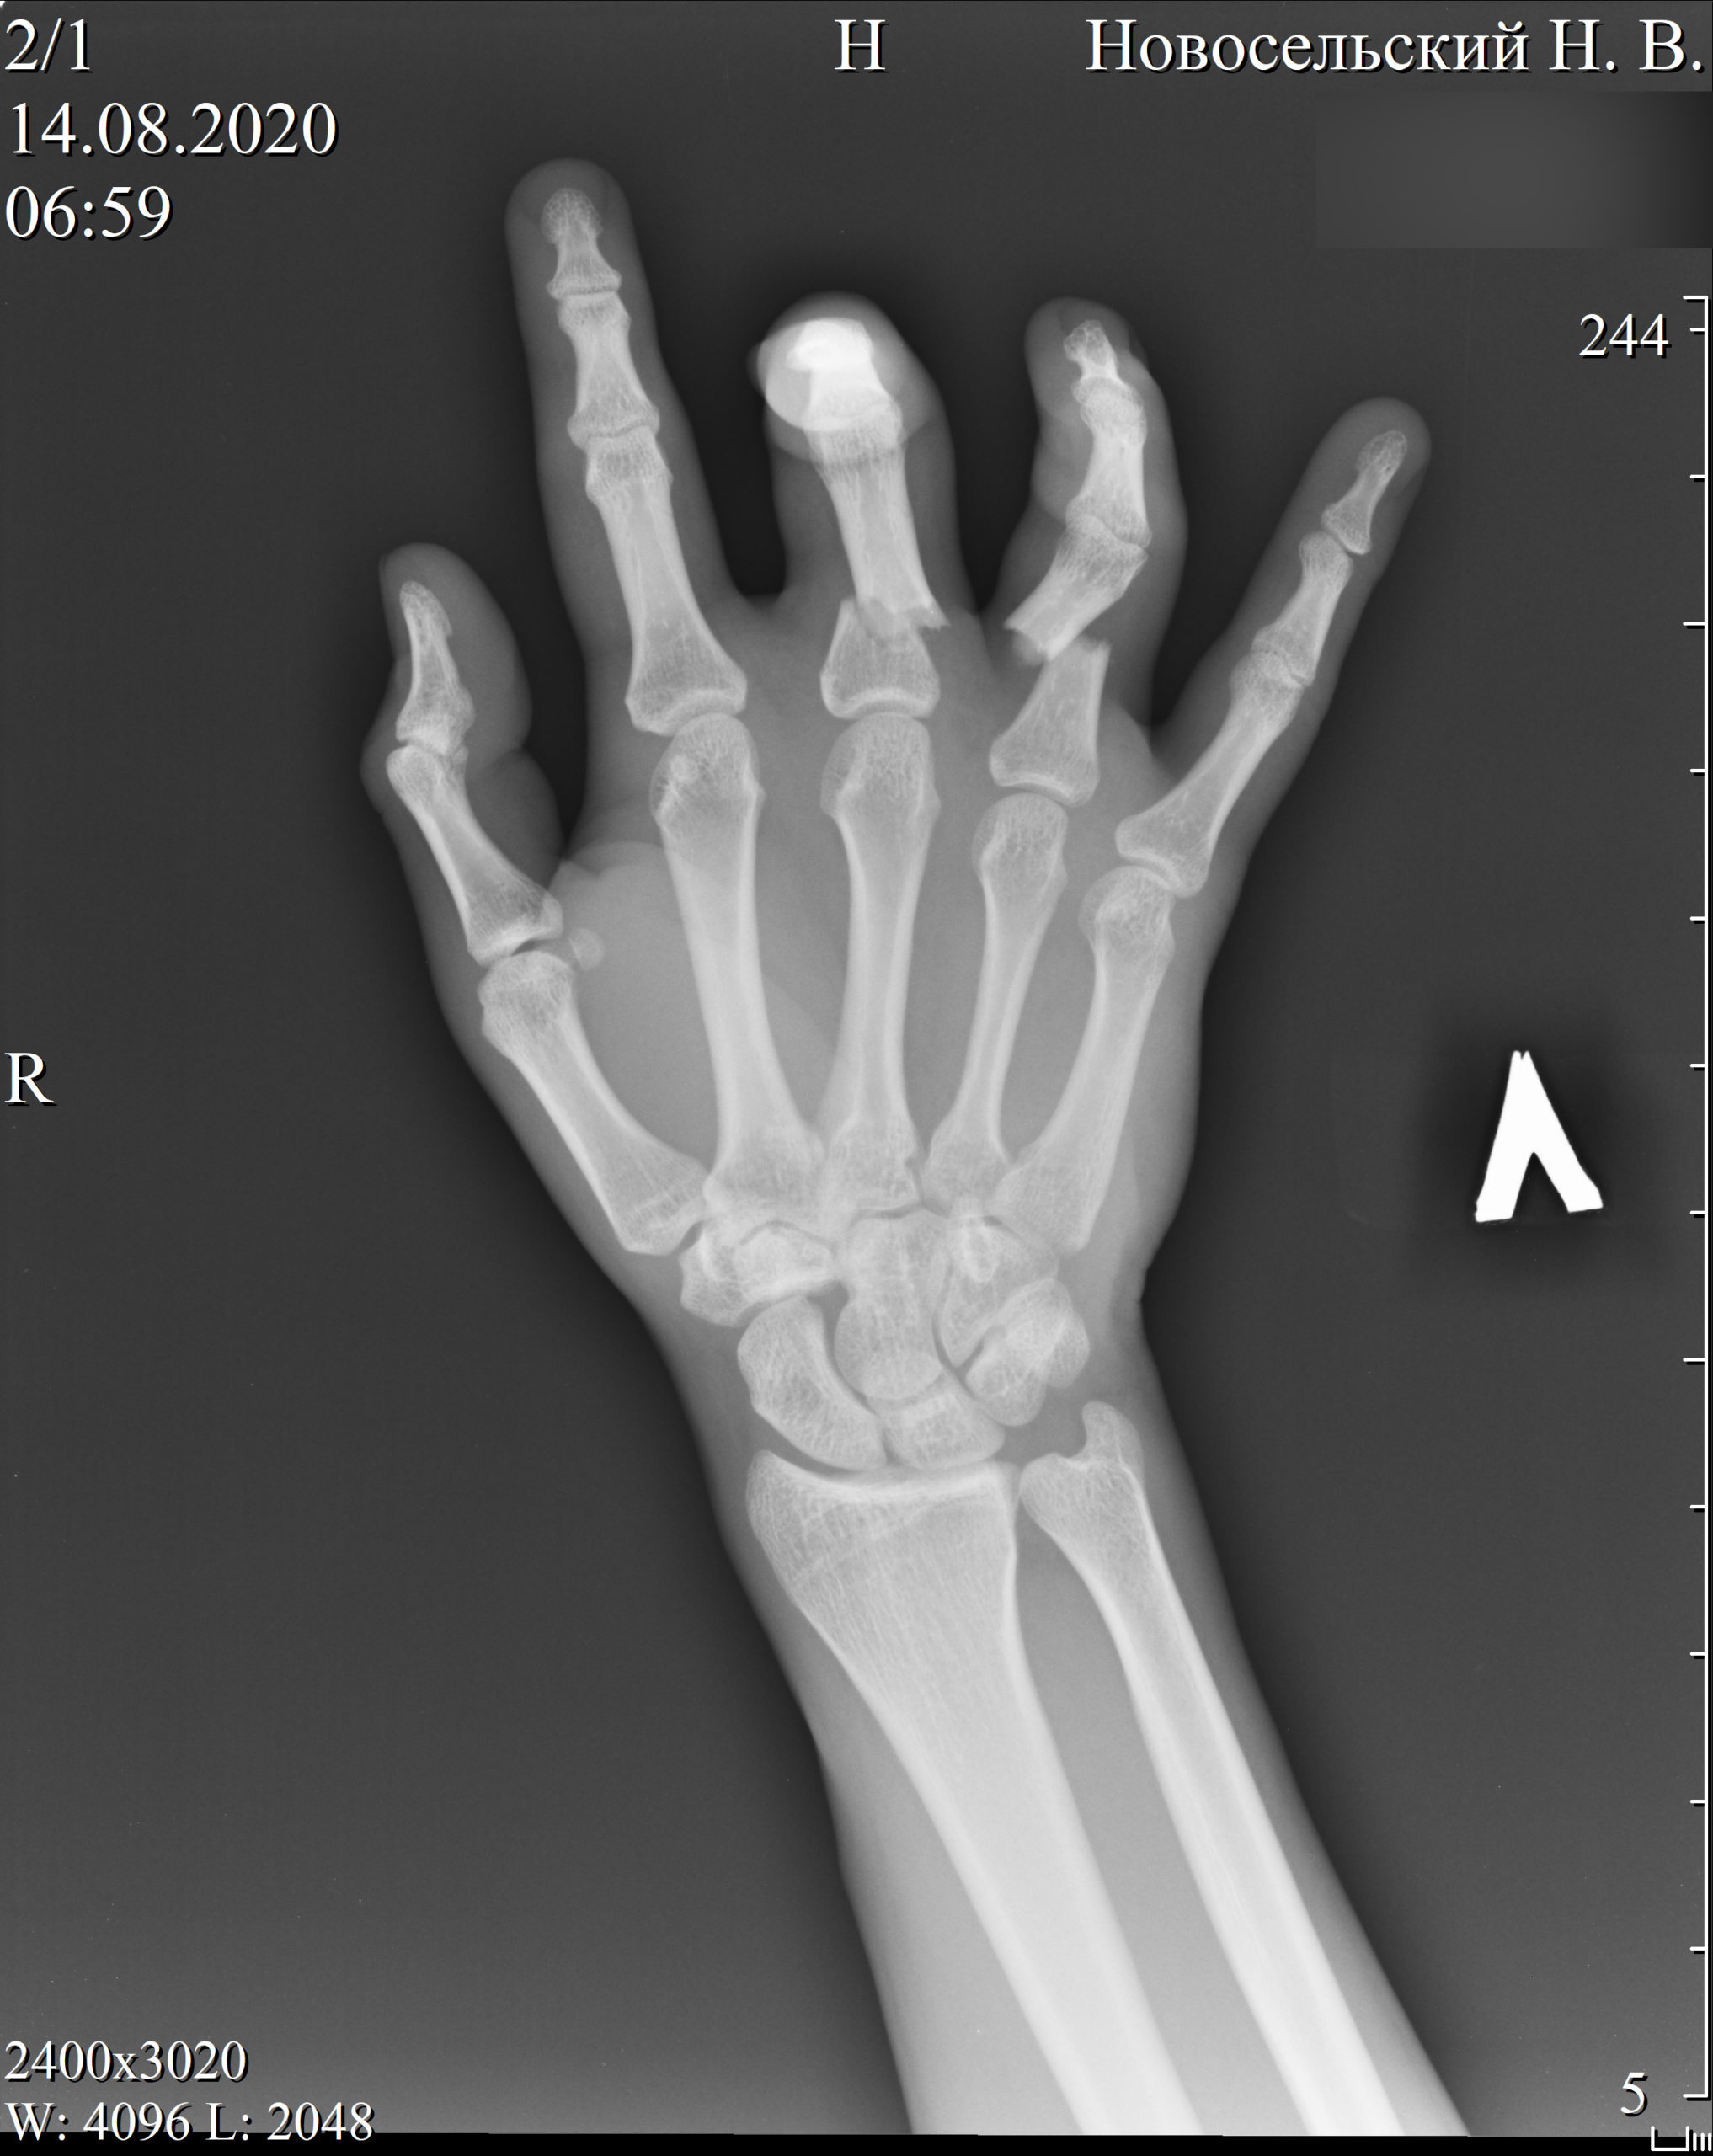

Рентгеновский снимок руки одного из заявителей, Николая Новосельского. Фото с сайта belarus.pytkam.net

История Николая Новосельского